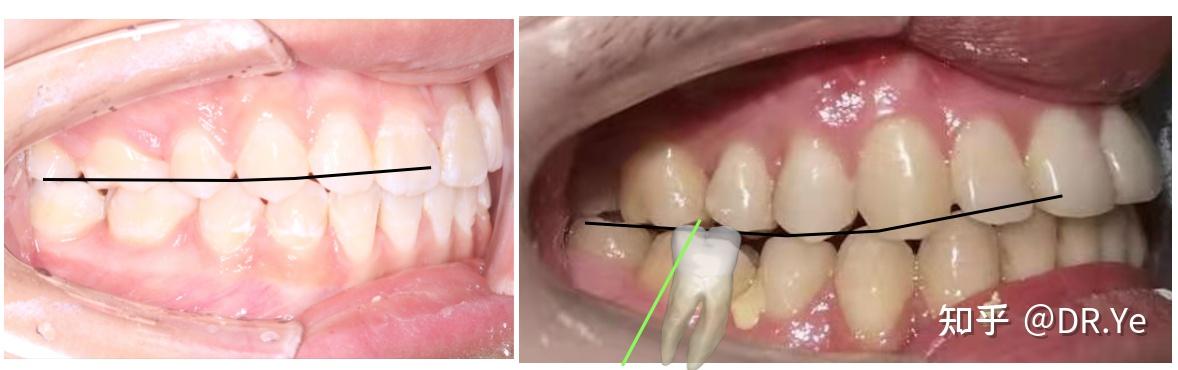

病案

仁爱口腔严重突面畸形的矫形治疗

在于上下牙列纵合曲线的控制(医生常说的spee(斯匹)曲线)绿线代表了